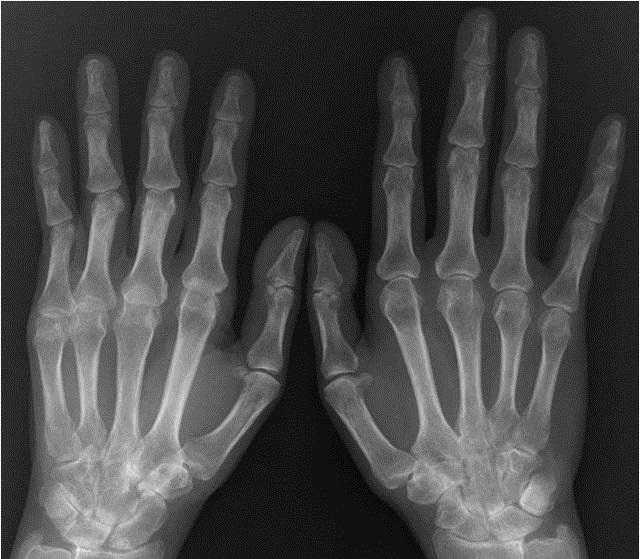

1、X线检查

这个在临床上不常用,一般见于年份较久的腱鞘囊肿或者体积较大甚至引起骨头压迫吸收的,用于将腱鞘囊肿与其他各种肿瘤相互区别。

要注意的是,如果只是单纯的腱鞘囊肿,拍了X线可能啥都看不到。X线的主要优点是看骨头,对软的东西他几乎是近视的!

看看下面的图片,是不是出了骨头,啥都看不到!